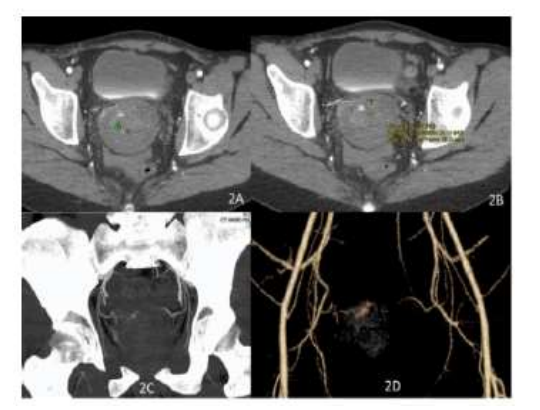

Jacques et al. [25] reported a 27-year-old year old null gravid lady, who was on warfarin anticoagulation in view of her having a mechanical tricuspid valve and underlying congenital heart disease, who manifested with sudden onset of profuse vaginal bleeding despite being on continuous oral contraceptive pills. She had been admitted on three separate occasions over a period of 3 months for the management of menorrhagia and overall, she had been transfused with 25 units of blood. During her initial assessment, she received high-dose intravenous oestrogen successfully and she was discharged home on oral contraceptive pill. Her vaginal bleeding recommenced many weeks subsequently and upon her admission she had examination of her pelvis which demonstrated a bluish mass at the apex of her vagina which was suspected to be an arteriovenous malformation (AVM). In view of the bleeding with utilization of hormones as well as a question of a possible mass within her vagina on examination, she had an MRI scan of pelvis which demonstrated blood products at varying stages that had expanded the endometrial cavity without any definite cause identified as well as no arteriovenous malformation (AVM) was identified (see figure 12). She underwent dilatation and curettage (D&C) as well as placement of levonorgestrel intra-uterine device. Pathology examination of the curetting demonstrated benign endometrium that had progestin effect. She was discharged home and she was well for one week until her intra-uterine device (IUD) was expelled and she re-commenced bleeding again from her vagina for which she was initially managed by means of placement of an etonogestrel implant. She was re-admitted one week later due to her profuse bleeding from her vagina that required blood transfusion. An attempt was made to treat her with leuprolide which did not produce any successful effect. She was on warfarin treatment, which was reversed, and she underwent laparoscopic hysterectomy. There was no suspicion of AVU during the operation. Pathology examination of the surgical specimen did not demonstrate any abnormalities within her uterus, cervix, and fallopian tubes. She was well for 4 weeks after her operation but she suddenly re-manifested with bleeding from her vagina that required utilization of wall suction for visualization of her vagina and cervix and the bleeding was observed at the right side of her vaginal cuff. Her vagina was packed with gauze and she had CT angiogram which demonstrated active arterial bleeding within the right side of the apex of her vagina which was suggestive of an AVM (see figure 13). She was transfused with 2 units of packed red blood cells and prothrombin complex concentrate (PCC) was used to reverse her anti-coagulation. She had angiogram which revealed active extravasation from her right uterine artery with an artery to venous fistula (see figure 14). Two coils had to be placed proximal to the part of the uterine vessel which had vaginal branches, and this emanated in successful obliteration of the AVMU as well as cessation of her vaginal bleeding. She was recommenced on heparin drip as well as warfarin pursuant to her operation; nevertheless, on the day her INR reached therapeutic range, she re-started having profuse vaginal bleeding again. PCC was utilized to reverse her anti-coagulation. She had right internal iliac arteriogram which demonstrated abnormal blush as well arterio-venous fistula (AVF) within the same region as before, near the previously embolized uterine artery (see figure 15). Embolization of her right uterine artery was undertaken with glue. Catheterization of multiple branches of the artery did not demonstrate any extravasation of contrast. She was recommenced on warfarin as well as on heparin drip subsequently until her INR had reached therapeutic range. She was subsequently discharged, and she did not develop any further bleeding from her vagina. At her 6-week post-operative follow-up assessment, her examination demonstrated a well healed, and intact, cuff of her vagina. A lesson that has been learnt from this case report is that if an AVM develops with bleeding following hysterectomy for AVM, selective angiography and embolization could be undertaken to obliterate the AVM and to stop the bleeding.

Figure 13: CT angiography done after hysterectomy prior to the first embolization by interventional radiology. Images showing high density (average Hounsfield Unit 73) acute blood/contrast in the pelvis (9B) with active arterial extravasation (9A). Active arterial extravasation is also seen nicely on maximum intensity projection (9C) and volume rendered (9D) images Reproduced from: [25] Jacques L, Lund M, Baruah D. Uterine Arteriovenous Malformation: A Rare Cause Vaginal Hemorrhage after hysterectomy. Gynecology & Obstetrics Case Report. 2016; 2(2): 1 – 4. doi:10.21767/2471-8165.1000029 https://gynecology-obstetrics.imedpub.com/uterine-arteriovenous-malformations-a-rare-cause-of-vaginal-hemorrhage-after-hysterectomy.pdf https://gynecology-obstetrics.imedpub.com/uterine-arteriovenous-malformations-a-rare-cause-of-vaginal-hemorrhage-after-hysterectomy.php?aid=11196